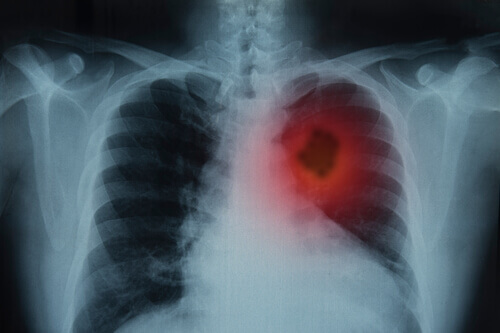

Se os sinais continuarem por mais de três semanas é indispensável que o paciente procure um médico para realizar uma radiografia na área do tórax.

Depois, com os resultados, realiza-se uma história clínica de maneira minuciosa, um exame físico e outros testes de laboratório.

Imagens

É um procedimento que permite capturar as áreas internas do corpo.